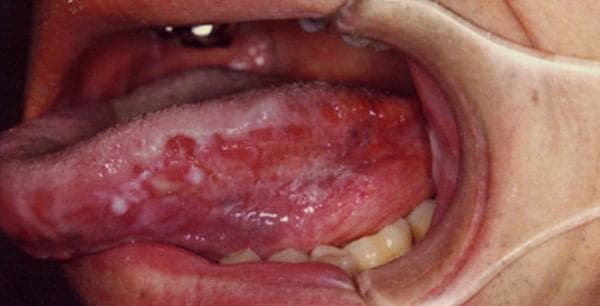

Hình ảnh ung thư lưỡi giai đoạn đầu

Hình ảnh ung thư lưỡi giai đoạn đầu giúp bạn đọc hiểu rõ hơn về căn bệnh này cũng như kịp thời phát hiện những bất thường để thăm khám sớm. Ung thư lưỡi giai đoạn sớm Ung thư lưỡi xuất phát ở phần lưỡi di động hay cố định (đáy lưỡi). Đây là loại […]